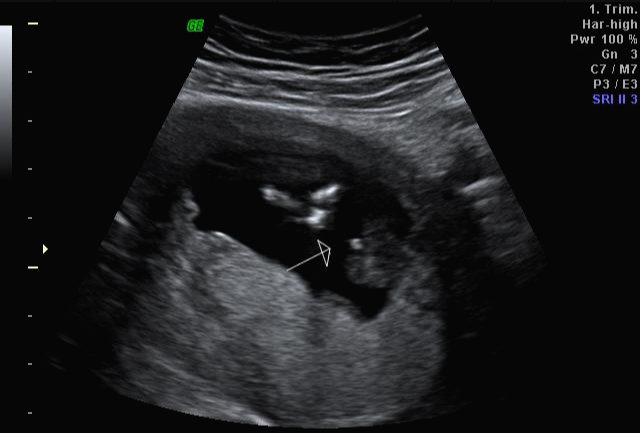

임신 17주 차 초음파 검사

한 달 뒤인 17차 때 다시 사설로 가서 초음파 검사를 받았는데 검사해주시는 분 께서 한참을 보시더라고요~ 그러면서 어떻게 보면 딸 같다고 하셔서... 응? 100프로 아들이라 해서... 다 아들껄로 준비하고 있는데.. 무슨 소리지? 하고 다시 한번 봐달라고 하니 아들이라 하시면서 위에 초음파를 보여주셨어요!

한데 기분이 참 찝찝했어요~ 뭔가 숨기고 있는 듯한.. 정확하지 않는 듯한 느낌 ㅋㅋㅋ... 그래서 임신 17주 차부터 아이 용품 구매하는 걸 중단하고 병원에서 20주 차 정밀 초음파 검사를 기다려 보기로... 가족도 다 아들로 알고 있고 벌써 아들 꺼 처럼 보이는 용품들로 준비했기 때문에 성별 반전이 없기를 기대했어요 ㅠㅠ